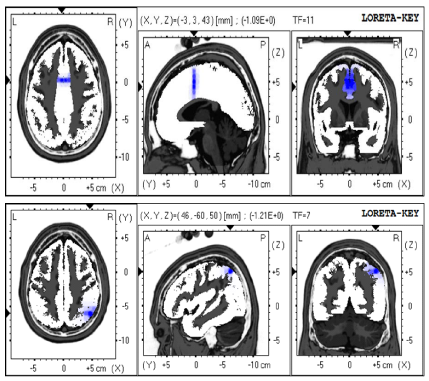

19year old male was brought for an appointment by his adoptive parents indicating problems with cognition, mostly executive function and information processing speed dysfunction. Initial QEEG revealed frontal increase in delta power however LORETA (Figure 7A) (Figure 8A) showed anterior cingulate electrical dysregulation. Before initiation of NFB, the neurocognitive testing was completed in March, 2013; results showed low cognitive score-Global Cognitive Score 80.2 with low executive function 87.2, and a very low information processing speed of 52.1. After the first 10 sessions of NFB, his executive function improved to 89.9, and with each round of ten NFB sessions, repeated cognitive testing was giving better results with executive function (subsequently 92 and 97; (Figure 9). In addition to improvement of LORETA (Figure 7B, 7C & 7D) electrical dysregulation as well as QEEG findings (Figure 8B, 8C & 8D) and cognitive testing, his parents noted a tremendous improvement with social and cognitive performance.

Figure 7a LORETA imaging of 19 year old patient showing area of electrical dysregulation of Anterior Cingulate (AC) region BA 32 (in red).

Figure 7b Resolution of AC dysregulation after 10 sessions of NFB.

Figure 7c Resolution of AC dysregulation after 20 sessions of NFB.

Figure 7d Resolution of AC dysregulation after 30 sessions of NFB.